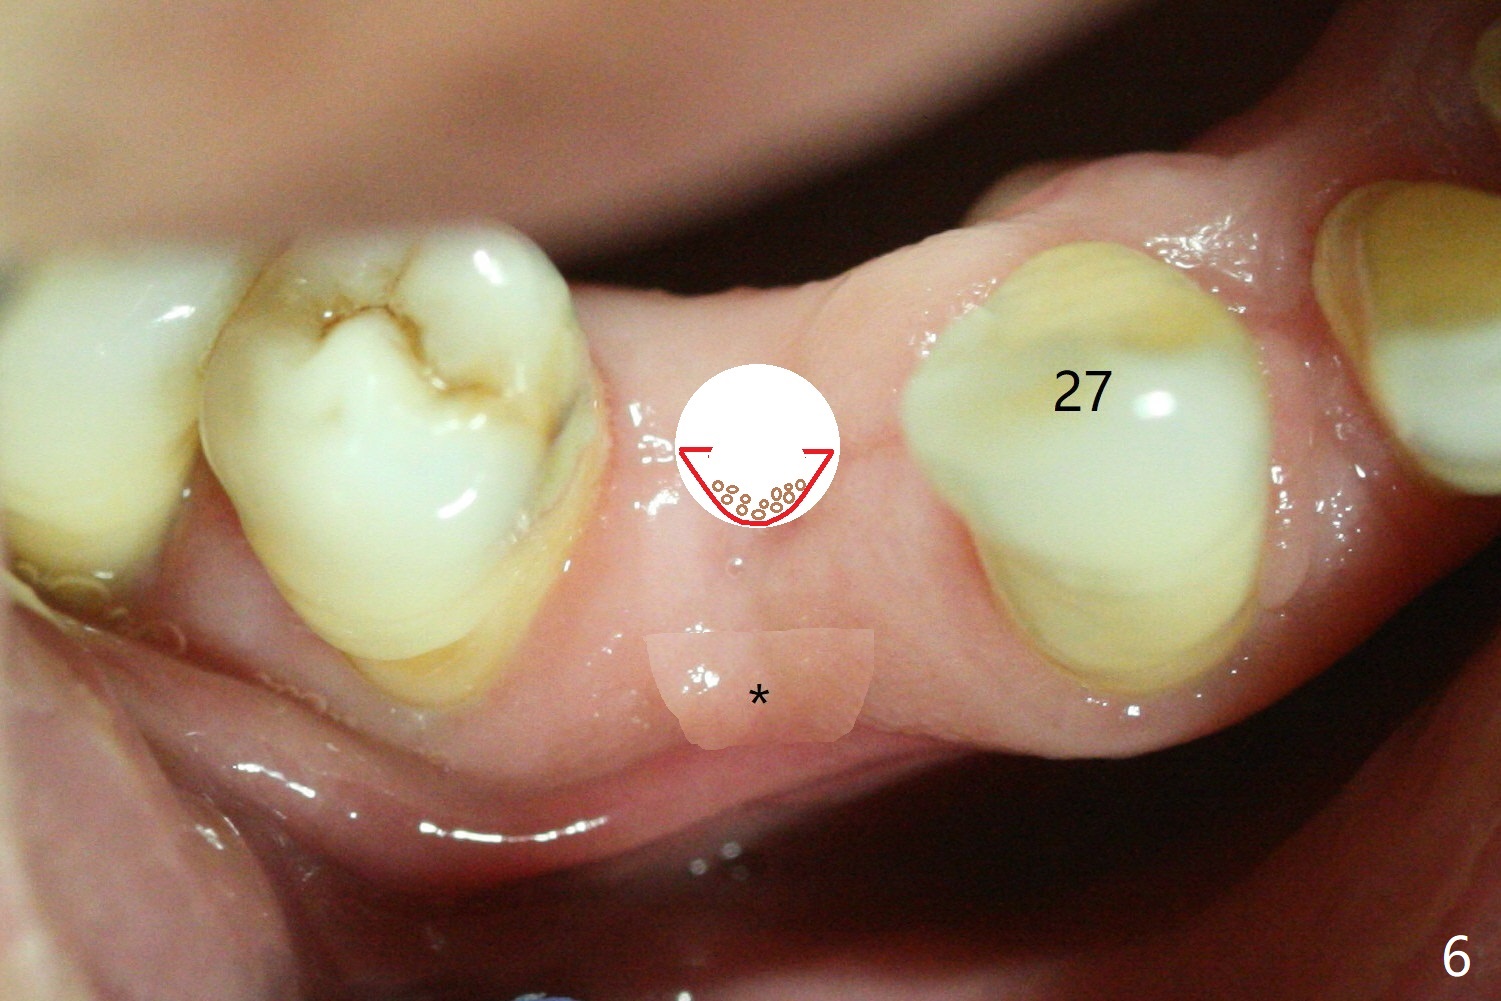

plate is further expanded buccally with a large expander (Fig.5). Bone graft

(Fig.6 red) is placed buccal.